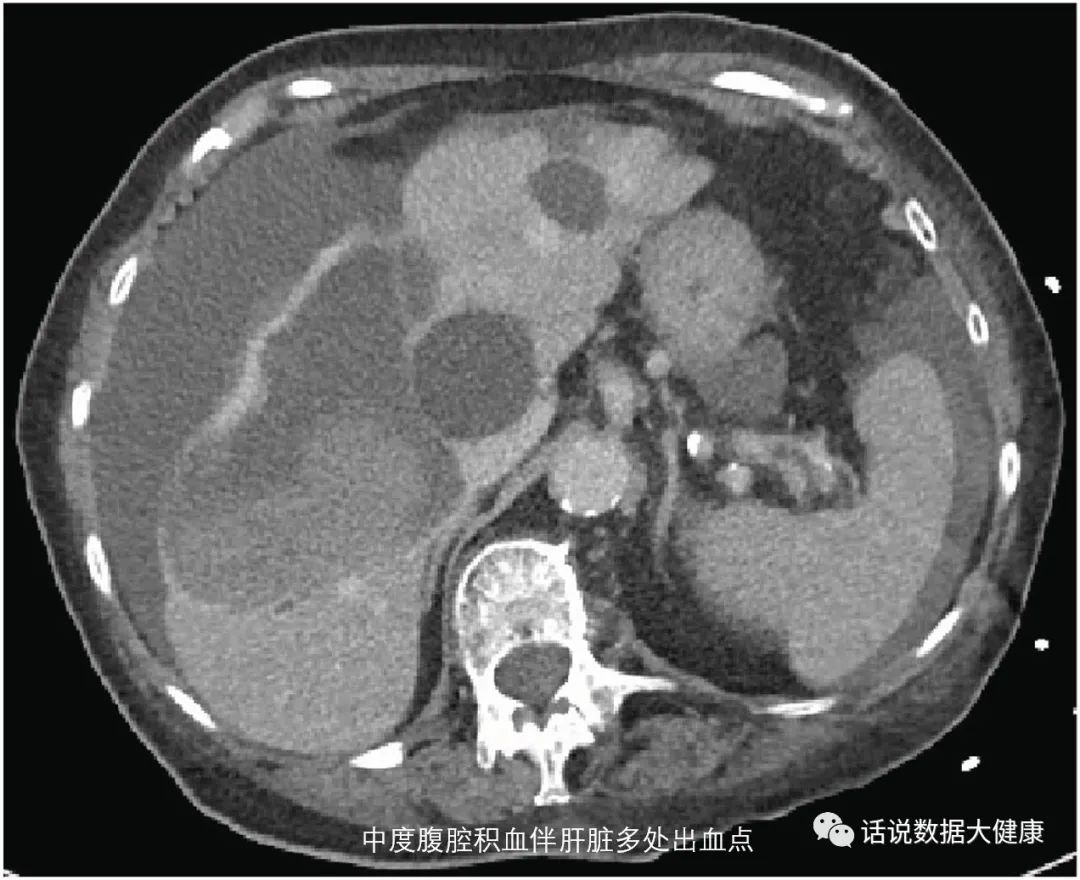

临床报道某女性,既往有阵发性房颤,未服用任何抗凝药, 每天服用纳豆激酶( 具体量不详)。因摔倒门诊查体发现腹腔内出血,入院后给与止血、输血等治疗,后因严重低血压去世。